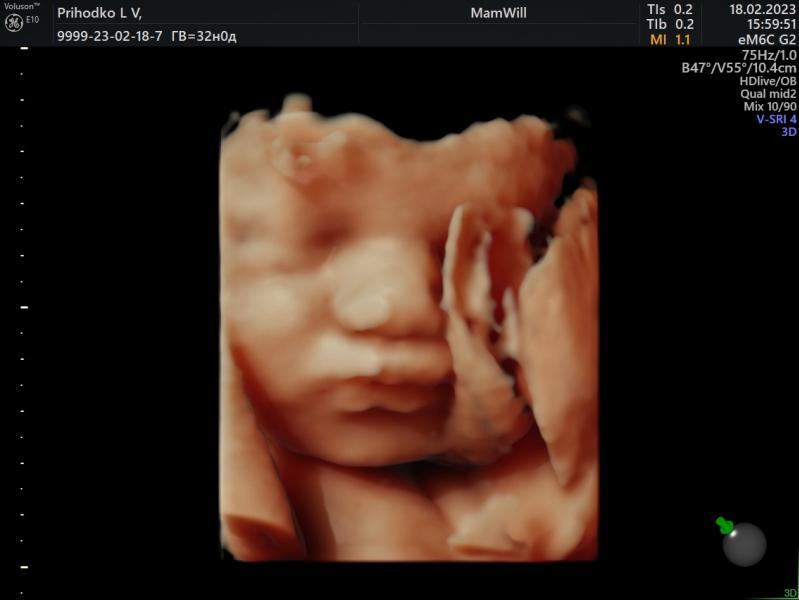

Сегодня прошла 3 скрининг

По месячным 32 недели, по узи 31,4

Вес 1864 г

Все в норме🤍

Даже волосики показали длинные😍

Мой губастенький мальчик не хочет переворачиваться(